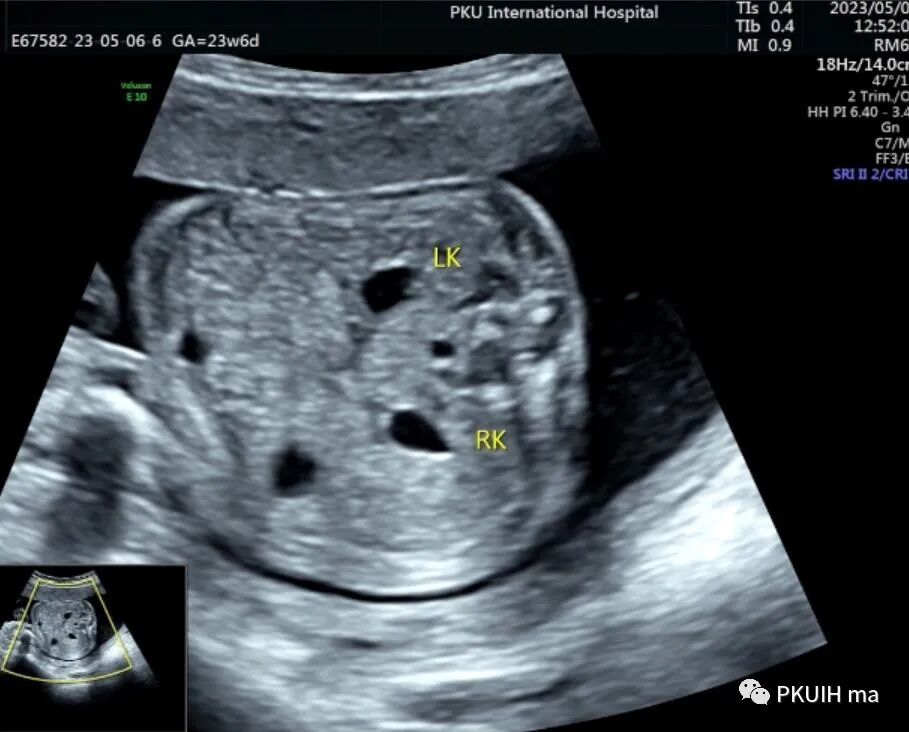

双肾横断面观察双肾盂轻微分离,肾门指向腹侧,呈倒“八”字征。(LK:左肾,RK:右肾)